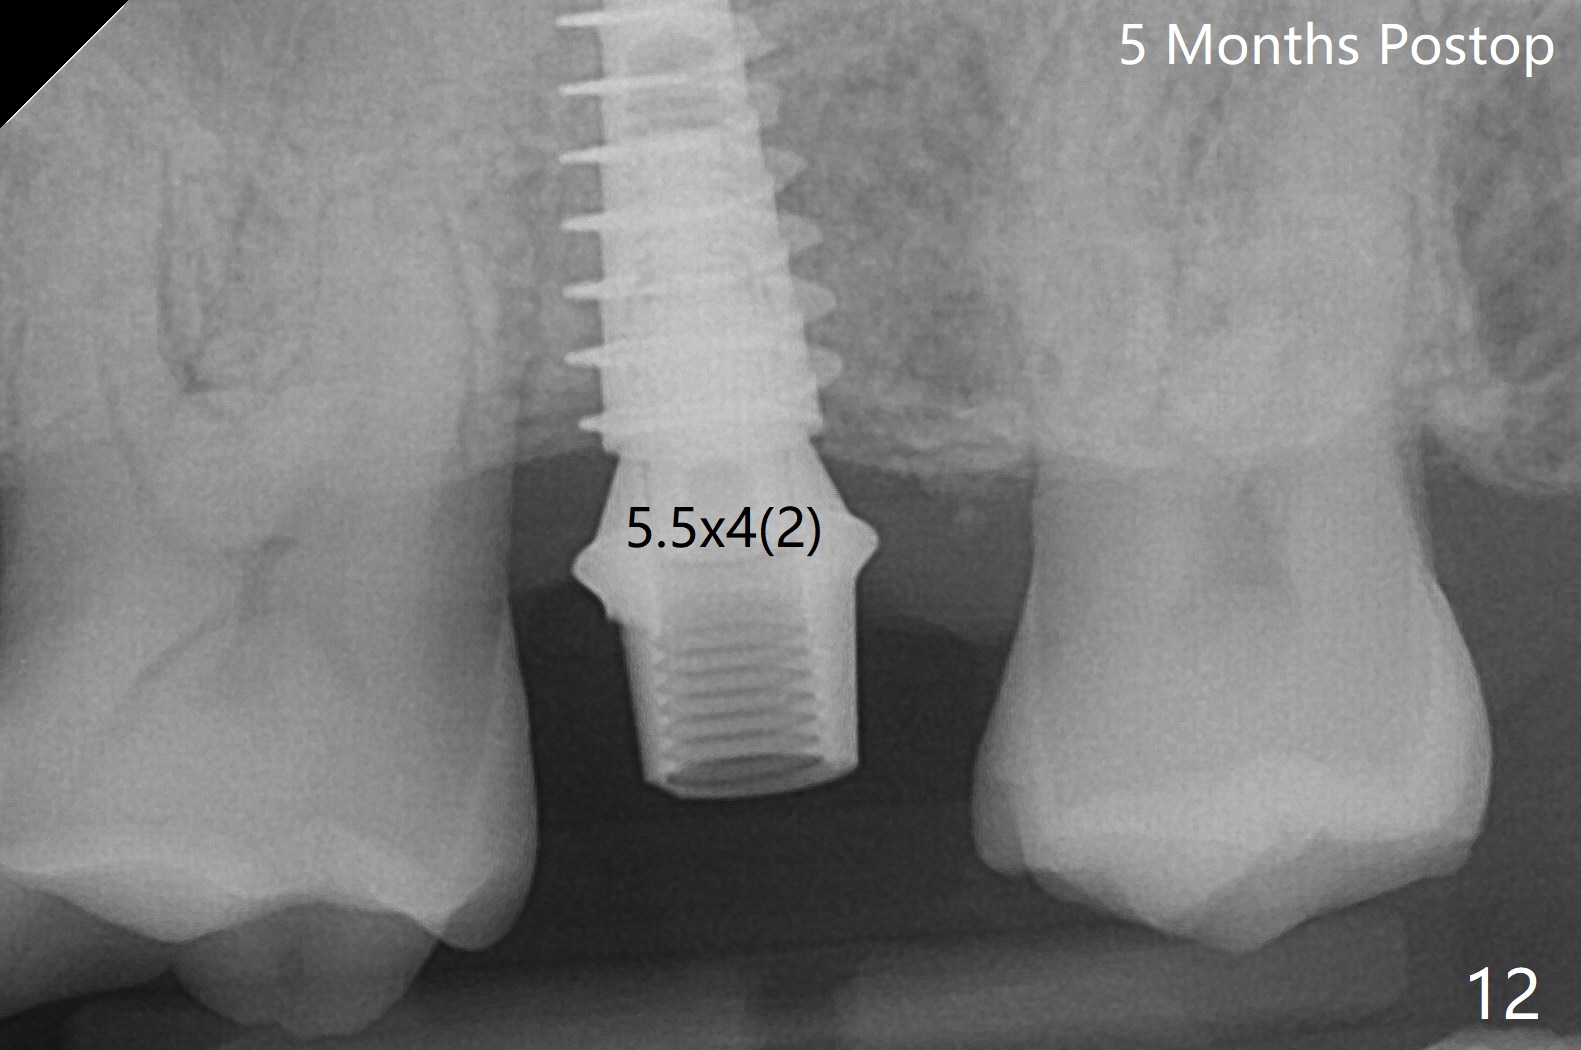

2号牙位点保存后6个月,而15号牙拔除没有植骨1-2年前(图一)。2号牙位骨质高度足够,准备不做上颌窦提升(图二),而15号牙位需要提升(图三,六)。种植术后5个月两个植体愈合均正常(图十一,十二)。